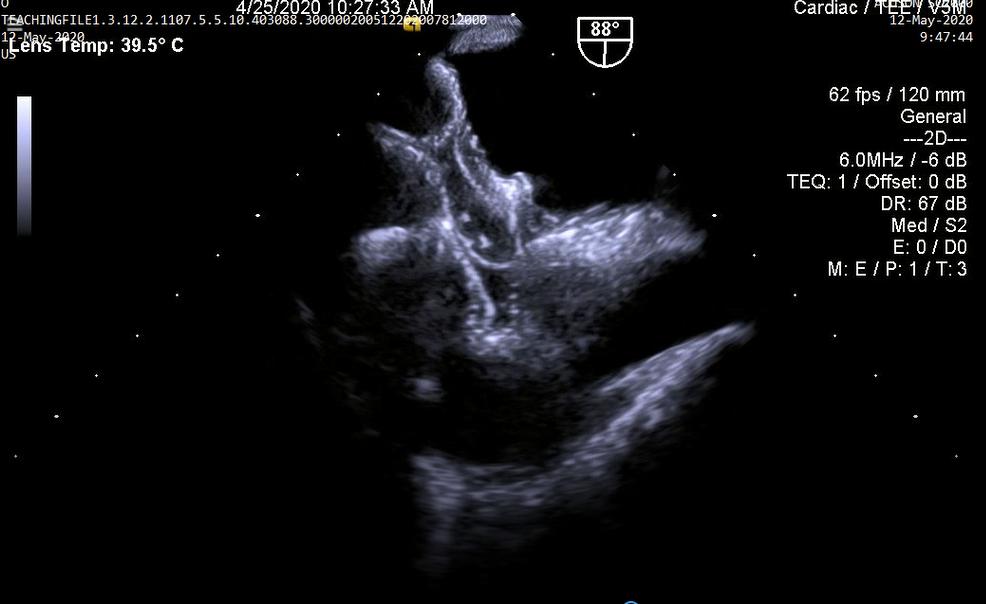

3.Huyết khối tiểu nhĩ trái trên bệnh nhân hẹp van 2 lá (không thấy được trên siêu âm tim qua thành ngực)